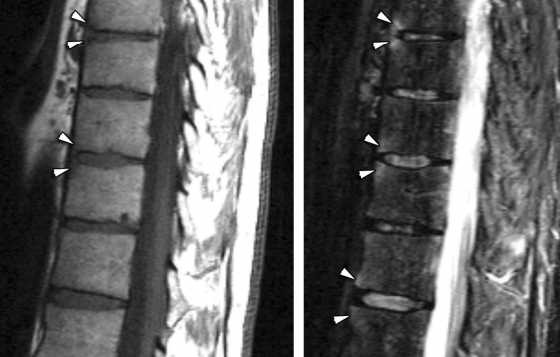

- Ossification des fibres marignales de l’anulus fibrosus (bamboo-spine)

- Mise au carré des vertèbres (Erosion des coins = Lésion de Romanus, évoluant en Sclérose avec aspect “Shiny”)

Colonne de bambou

Lésion de romanus